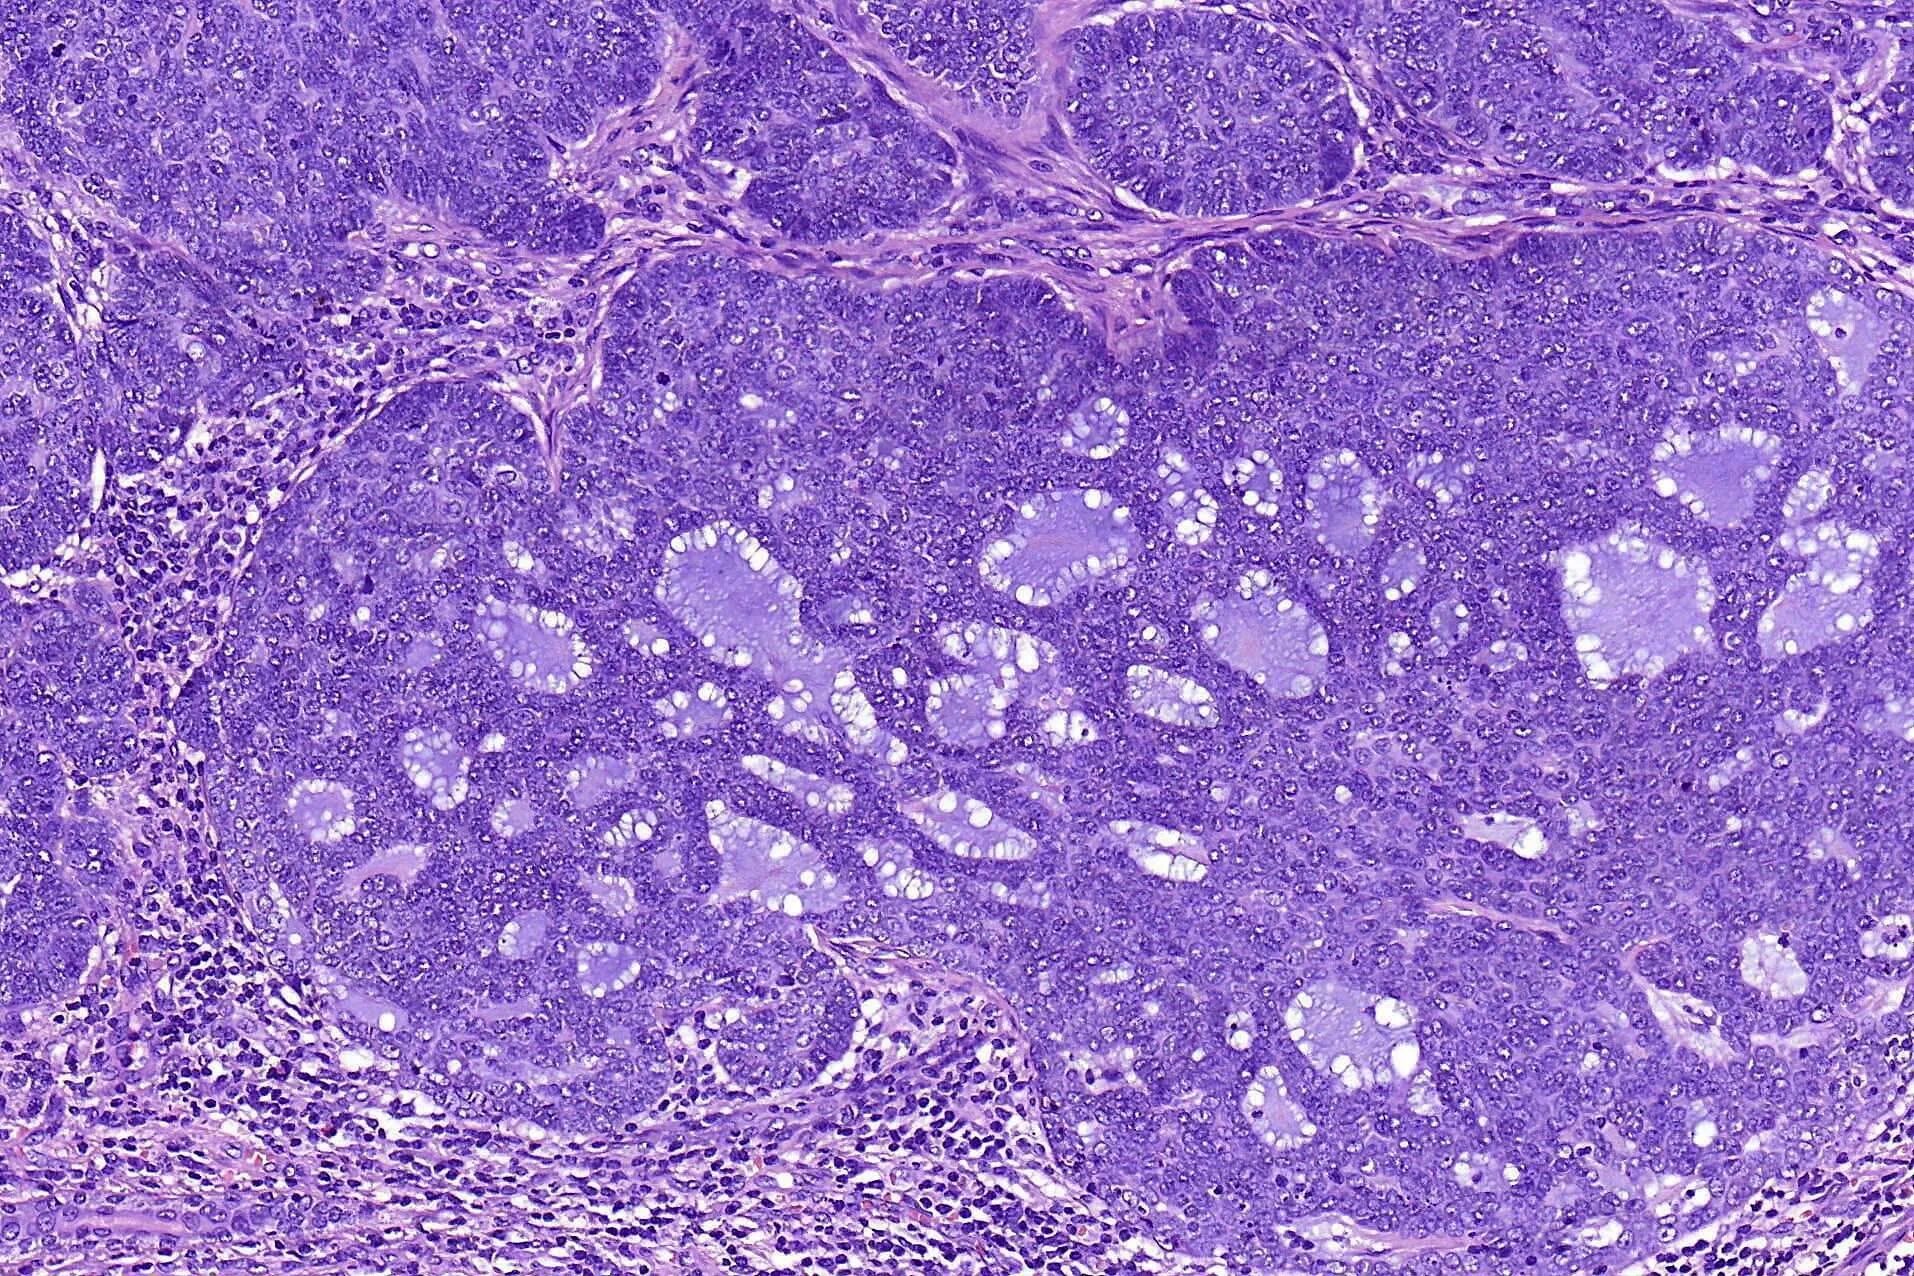

Гистология базалиома